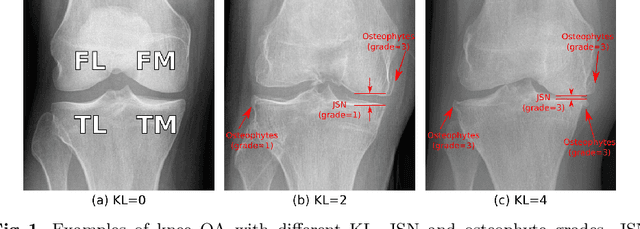

Abstract:Knee osteoarthritis (OA) is a common degenerate joint disorder that affects a large population of elderly people worldwide. Accurate radiographic assessment of knee OA severity plays a critical role in chronic patient management. Current clinically-adopted knee OA grading systems are observer subjective and suffer from inter-rater disagreements. In this work, we propose a computer-aided diagnosis approach to provide more accurate and consistent assessments of both composite and fine-grained OA grades simultaneously. A novel semi-supervised learning method is presented to exploit the underlying coherence in the composite and fine-grained OA grades by learning from unlabeled data. By representing the grade coherence using the log-probability of a pre-trained Gaussian Mixture Model, we formulate an incoherence loss to incorporate unlabeled data in training. The proposed method also describes a keypoint-based pooling network, where deep image features are pooled from the disease-targeted keypoints (extracted along the knee joint) to provide more aligned and pathologically informative feature representations, for accurate OA grade assessments. The proposed method is comprehensively evaluated on the public Osteoarthritis Initiative (OAI) data, a multi-center ten-year observational study on 4,796 subjects. Experimental results demonstrate that our method leads to significant improvements over previous strong whole image-based deep classification network baselines (like ResNet-50).